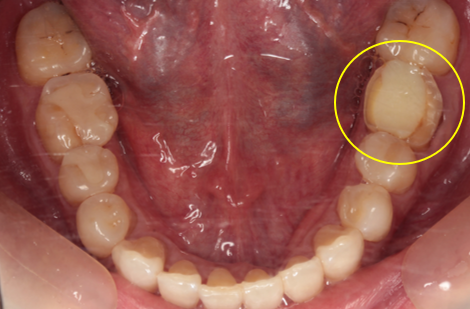

39歳男性